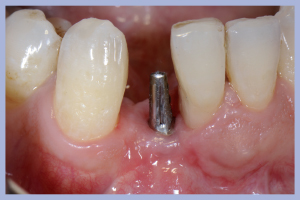

Liberiamo un lembo linguale e un lembo vestibolare “a scorrimento” che ci permetterà di coprire tutto il letto operatorio. La visione incisale ci permette di identificare l’alveolo dentale dell’elemento 4.1 completamente conservato e collocato mesialmente adiacente all’elemento 3.1. Diversamente il sito alveolare dell’elemento 4.2 risulta mancante della parete linguale e dislocato linguo-distalmente al precedente (Fig. 3).

- Fig. 3

- Fig. 3a

- Fig. 3b